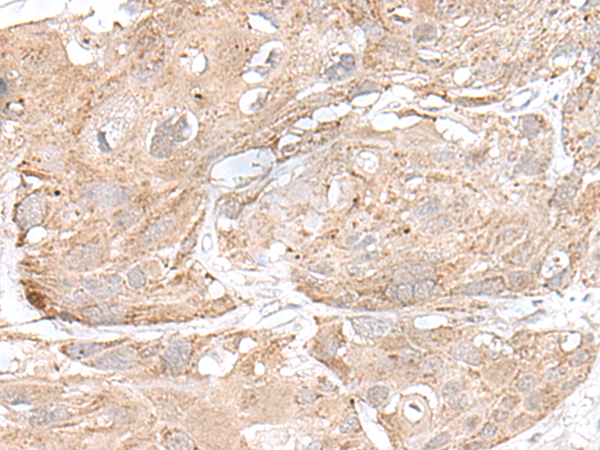

分类: 科研抗体货号: P09826别名: PRL3; PRL-3; PRL-R应用: IHC反应种属: Human